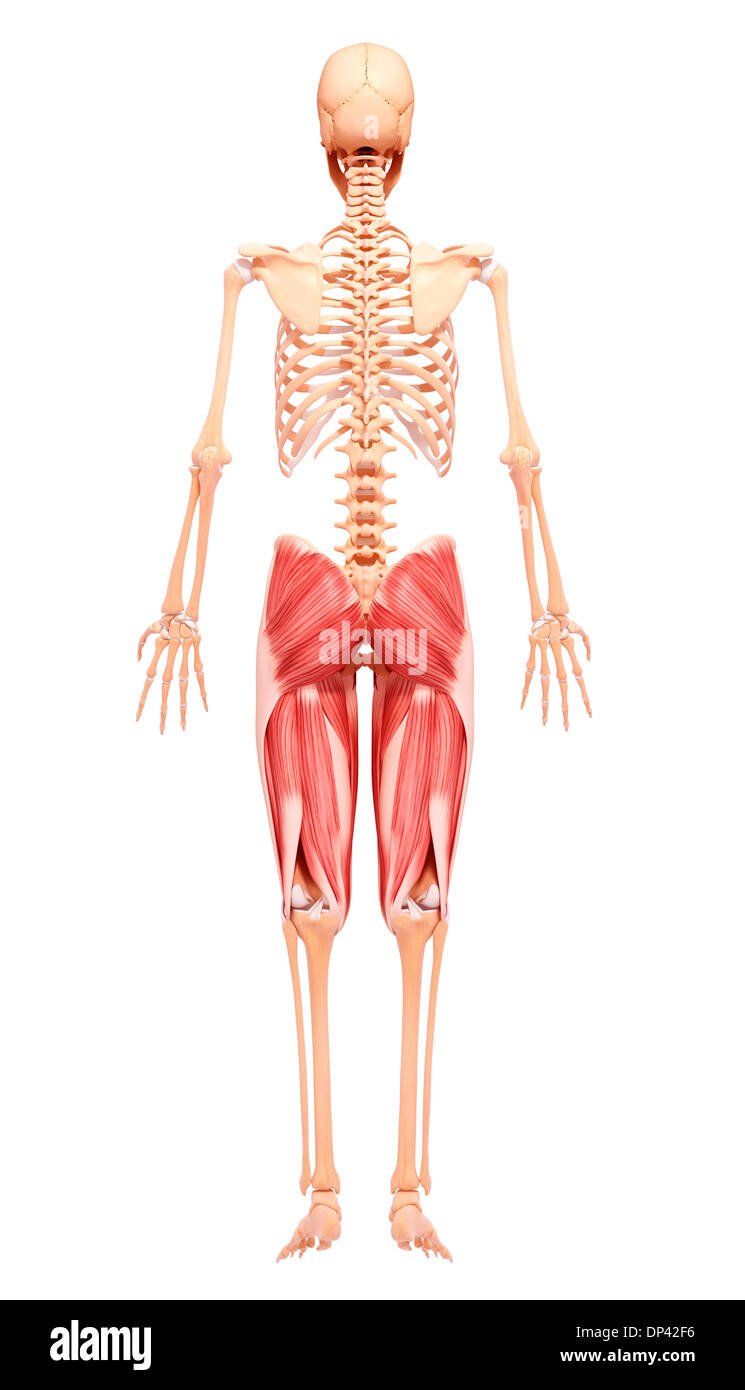

Human foot anatomy, artwork Banque D'Imageshttps://www.alamyimages.fr/image-license-details/?v=1https://www.alamyimages.fr/human-foot-anatomy-artwork-image65243338.html

Human foot anatomy, artwork Banque D'Imageshttps://www.alamyimages.fr/image-license-details/?v=1https://www.alamyimages.fr/human-foot-anatomy-artwork-image65243338.htmlRFDP42F6–Human foot anatomy, artwork